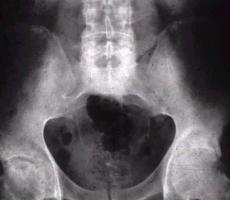

Cuando el cartílago cotiloídeo y de la cabeza femoral van disminuyendo de altura, se va produciendo una esclerosis subcondral, que representa una forma de reacciones del hueso ante la falla del cartílago hialino. Sobre los 55 años se pueden observar ulceraciones y erosiones que dejan al hueso subcondral sin su cubierta cartilaginosa, sin que medie ninguna alteración patológica conocida, sólo debido al uso (envejecimiento articular). Otro sintoma de la esclerosis subcondral es la disminución de altura del cartílago por fenómenos degenerativos, que se traduce en estrechamiento del espacio articular, que en las radiografías aparece como una línea nítida más blanca (mayor densidad ósea), en la zona de mayor presión y zonas hipodensas llamadas geodas, tanto en el cótilo como en la cabeza femoral.

La esclerosis subcondral es un signo radiológico, es decir que se demuestra en las placas de rayos de las articulaciones; que es el resultado de una respuesta reactiva del hueso y que se manifiesta como aumento de la densidad ósea del hueso subyacente al cartílago articular (esto es inmediatamente debajo de la articulación).

Es típico de la artrosis, pero también puede presentarse en otras patologías. La artrosis es una patología degenerativa que afecta sobretodo a articulaciones móviles (cadera, columna, mano, rodilla) y que se produce por la alteración de las propiedades del cartílago y del hueso subcondral, es el resultado de un grupo de patologías múltiples con manifestaciones similares y principalmente del desgaste articular de la edad.